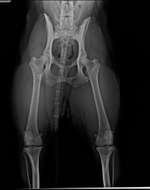

unser 14-jähriger Mischling hat seit nun mehr 2 Jahren andauernden Husten.

Folgendes wurde gemacht (und ausgeschlossen):

- 3 Endoskopien, Ausschluss Trachealkollaps und Kehlkopflähmung, es besteht der Verdacht auf Stimmbandlähmung, sei wenn dann aber nur minimal

- Abklärung durch Kardiologe ...